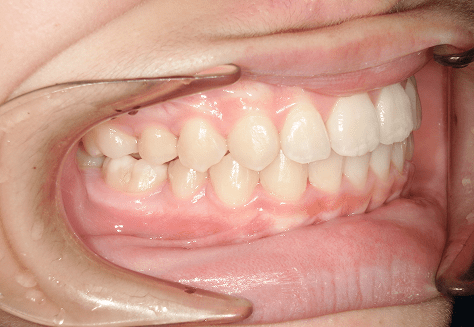

M.U

治療前

治療後

主訴

下の歯が特にガタガタなのが気になる。上の前歯が1本反対になっている。

診断

下顎前突・叢生・反対咬合

年齢/性別

20代/男性

抜歯部位

非抜歯

使用装置

上下インビザライン(PBM使用)

保定装置

ビベラリテーナー

料金

初回資料採得・・・・・・・30,000円

診断料・・・・・・・・・・33,000円

動的治療終了時資料採得・・5,500円 -

基本料金

950,000円

診察料金

5,500円×16回

-

治療期間

1年7カ月